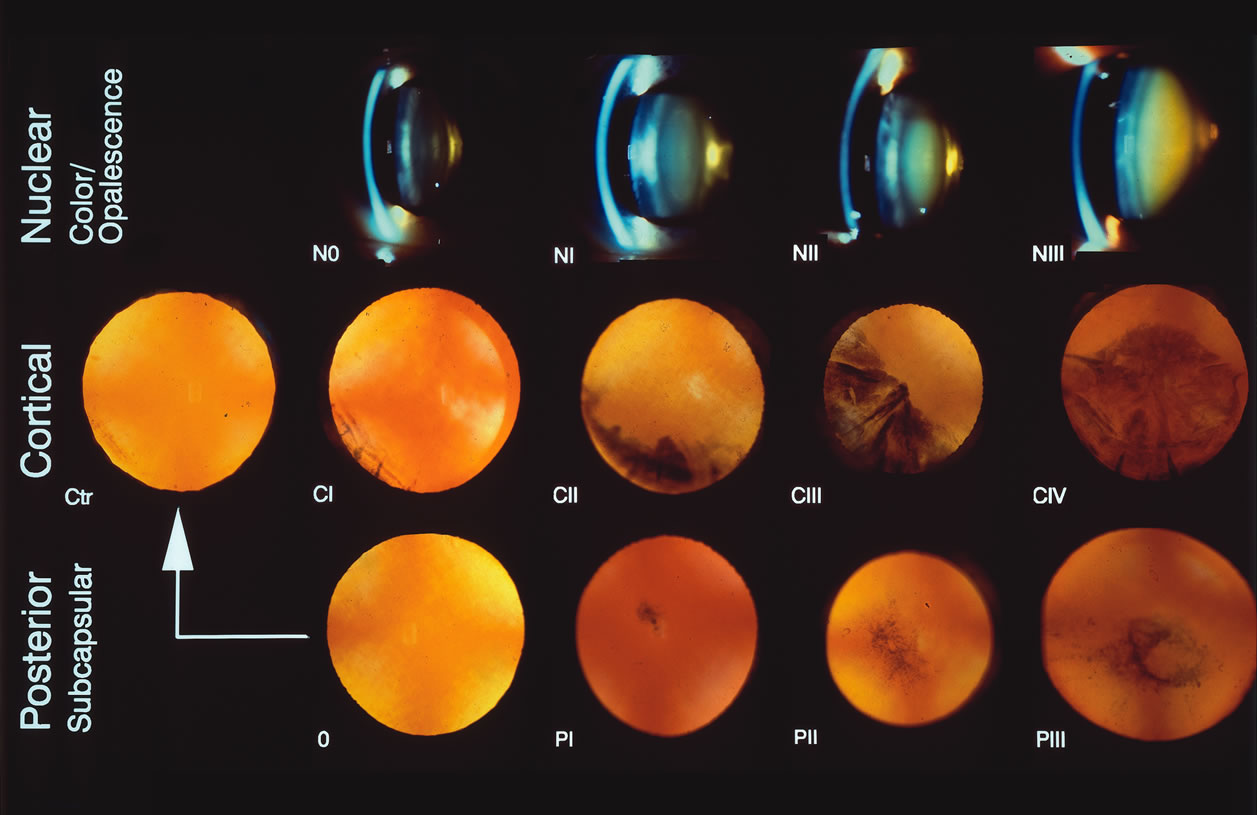

Fig. 7. The Lens Opacity Classification System II (LOCS II) photographic

grading standards. N = Nuclear photographs. Stage 0 = normal; I–III = various stages of nuclear cataract. For

nuclear opalescence, the average opalescence across the entire nuclear

region is used. An opalescence that is less than or equal to Photographic

Standard 0 = grade 0; if the opalescence is less than or

equal to Standard I, the grade is 1, and so on. For Color Grading of the

nucleus, only the N2 standard is used. (<N2 for color=0, equal

to N2 in color=1, and N2 for color = 2) C = Cortical

photographs. 0-Trace (Tr) = normal; I–IV = various steps of cortical cataract (roughly

CII

Fig. 7. The Lens Opacity Classification System II (LOCS II) photographic

grading standards. N = Nuclear photographs. Stage 0 = normal; I–III = various stages of nuclear cataract. For

nuclear opalescence, the average opalescence across the entire nuclear

region is used. An opalescence that is less than or equal to Photographic

Standard 0 = grade 0; if the opalescence is less than or

equal to Standard I, the grade is 1, and so on. For Color Grading of the

nucleus, only the N2 standard is used. (<N2 for color=0, equal

to N2 in color=1, and N2 for color = 2) C = Cortical

photographs. 0-Trace (Tr) = normal; I–IV = various steps of cortical cataract (roughly

CII  ¼, CIII ¼, CIII  ½, CIV ½, CIV  ¾. CV > ¾). P = Posterior subcapsular photographs. 0 = normal; I–III = various stages of posterior

subcapsular cataracts (Chylack LT, Leske MC, McCarthy D, et

al: Lens opacities classification system II [LOCS II]. Arch

Ophthalmol 107:991, 1989. Copyright 1989, American Medical Association

with permission.) ¾. CV > ¾). P = Posterior subcapsular photographs. 0 = normal; I–III = various stages of posterior

subcapsular cataracts (Chylack LT, Leske MC, McCarthy D, et

al: Lens opacities classification system II [LOCS II]. Arch

Ophthalmol 107:991, 1989. Copyright 1989, American Medical Association

with permission.)

as inclusion in a patient's chart. Recently, cataract classification systems have been developed that use

carefully selected slit lamp photographs of cataracts as standards for

comparison with the patient's cataracts. These include the following: the

Lens Opacities Classification System (LOCS) version

I,51 version II (Fig. 7),52 and version III,53 the Wisconsin Cataract Grading system,54 the Wilmer Cataract Grading System system,55 the Oxford Cataract Grading System system,56 and the Age Related Eye Diseases Study (AREDS) Cataract Grading

System.57,58 These systems are similar in that they provide lens photographs or films

showing various severities or grades of cortical, nuclear and posterior

subcapsular cataracts to be used as standards, which a clinician

can then compare to the patient's cataract as seen directly on the

slit lamp. For nuclear cataracts, slit photographs of the lens are used, and

for cortical and posterior subcapsular cataracts, retroillumination

photographs are used. Instructions are provided for the clinical

use of the systems, specifically what borders or cutoff points are to

be used for using each standard image. Figure 7 shows the LOCS II standard photographic plate. Another recently described